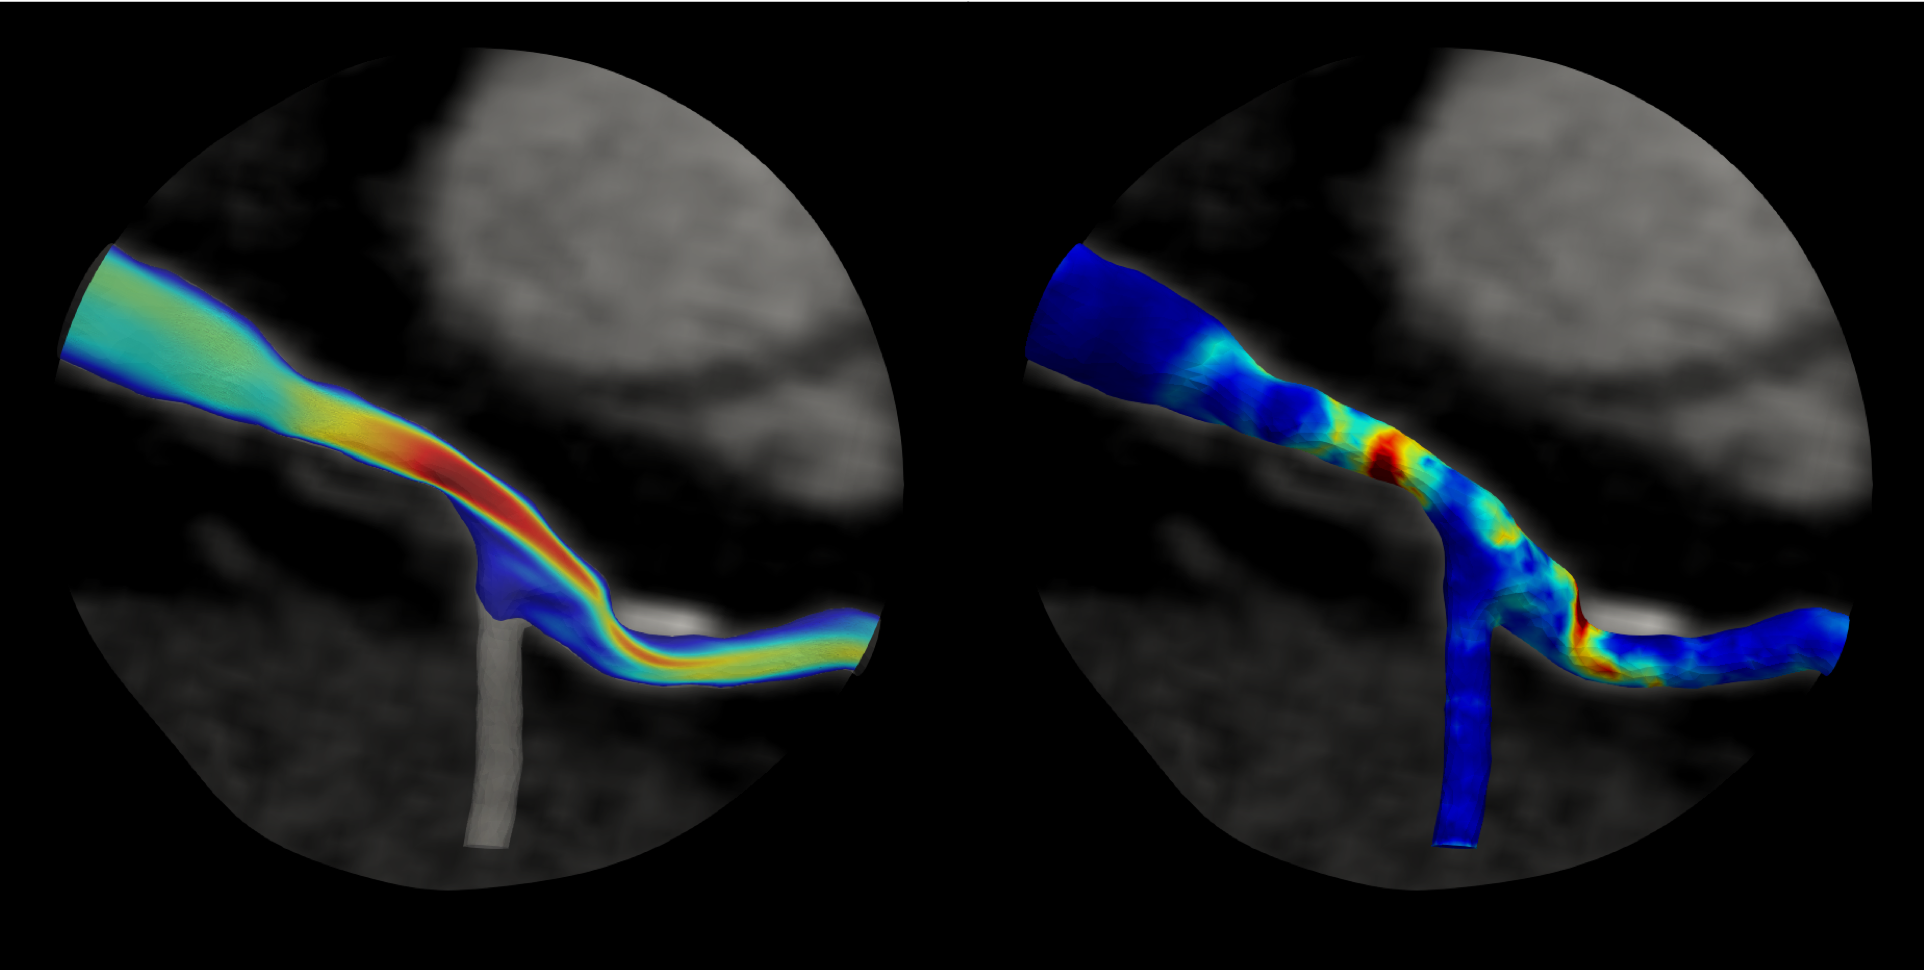

New funding will enable researchers to better understand blood flow (left) and pressure gradient (right) in heart artery blockages. Credit: HeartFlow

The new insights gained from this project will integrate lesion geometry, plaque characteristics and hemodynamic (blood flow) forces into a biomechanical stress analysis aided by deep-learning artificial intelligence methods and could lead to improved noninvasive simulation-based tests to better identify coronary artery plaques at risk of rupture in individual patients.